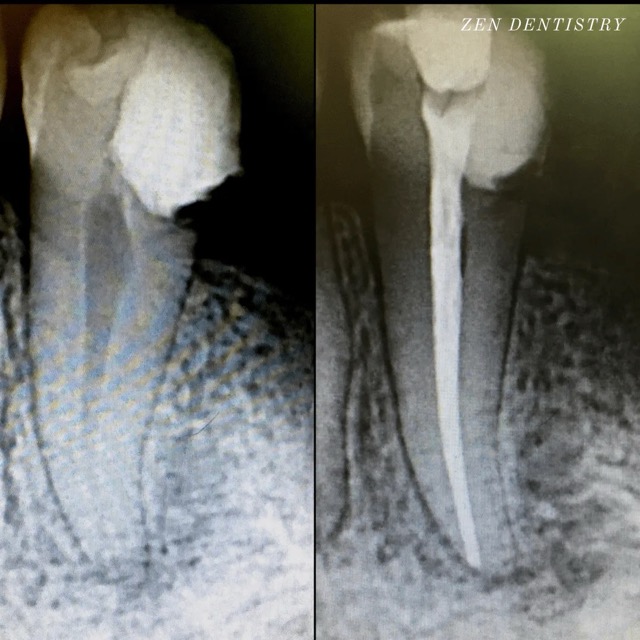

A thorough clinical exam, endodontic screening and proper x rays led to the diagnosis of irreversible pulpitis(inflamed pulp tissue) due to secondary dental caries with inflamed periodontal ligaments.

Our Dentists used the latest technology and highest quality products to finish this beautiful root canal followed by a post and core to give the tooth additional strength. The tooth was crowned after the root canal to restore function and aesthetics.